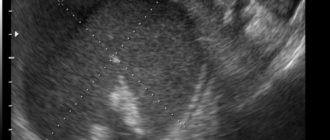

Эндометриоидная Киста левого яичника (операция)

Эндометриоидная киста яичника. Лечение без операции Эндометриоидная киста яичника образуется в придатках матки в

Эндометриоидные кисты

Эндометриоидная киста яичника Эндометриоидная киста яичника – это патологическое полостное образование на поверхности яичника,